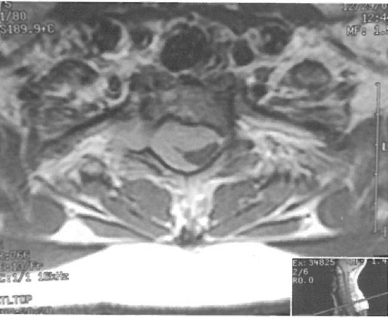

位于C7至T2节段的髓外硬膜内肿瘤包绕脊髓(图1和2)。

图2 切除椎板及右侧小关节突以暴露肿瘤。